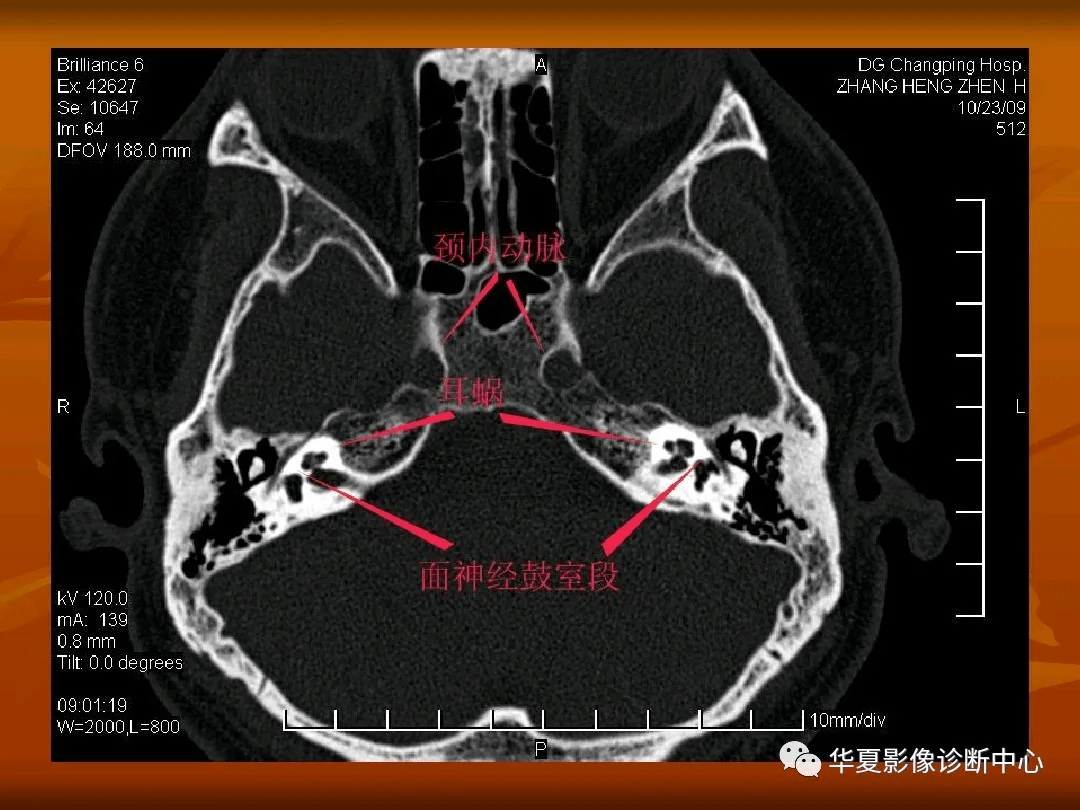

颅底ct高清图解 常见骨折部位图示